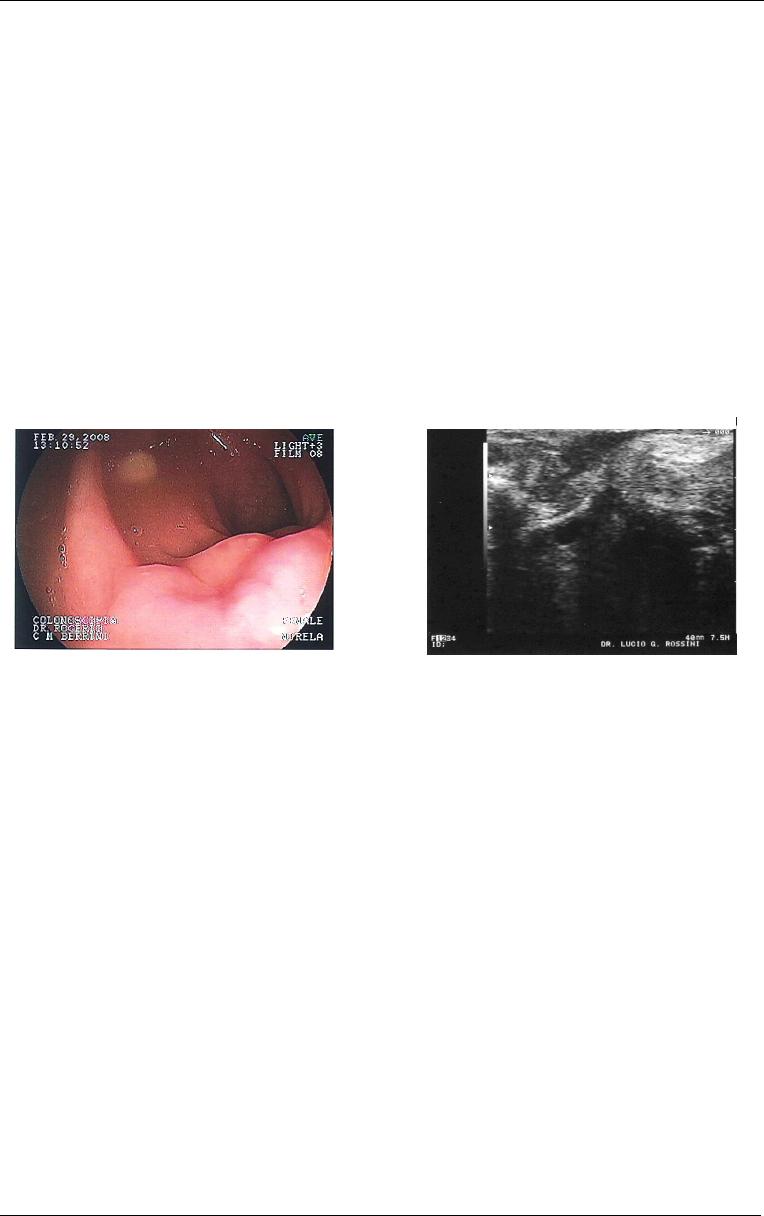

A endossonografia intestinal é aplicada com sucesso no diagnóstico de lesões

submucosas do cólon, apresentando melhor especificidade quando associada à

punção para biópsia por aspiração guiada por ecoendoscopia (Giovannini et al, 1993;

Kameyama et al, 1997; Hara et al, 2003) ou a biópsias realizadas depois da secção

da camada mucosa com bisturi elétrico, respaldada pela prévia observação da

localização submucosa da lesão por ecoendoscopia (Catalano, 1994) (Figuras 14 e

15).

Figura

1

5

- Imagem de ecoendoscopia

(sete e meio megahertz) com punção

evidenciando espessamento da camada

muscular própria intestinal e a extremidade

distal da agulha de punção (seta). Obs:

imagem cedida por Dr. Lucio Rossini.

14

- Imagem de endossonografia

intestinal (sete e meio megahertz)

muscular própria de segmento intestinal

(seta) decorrente de endometriose

intestinal. Obs: imagem cedida por

Dr.Lucio Rossini.